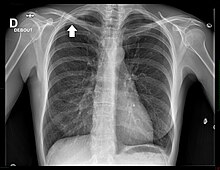

Radiographie thoracique

La radiographie thoracique est un examen de dépistage aisément accessible. Cependant, les tumeurs de l'apex de petite taille sont difficiles à visualiser en raison des superpositions osseuses de la clavicule et de la première côte[18].

Le cliché thoracique de face retrouve le plus souvent un simple épaississement de l'apex thoracique, ou bien une authentique masse pulmonaire englobant l'apex[20]. Une ostéolyse des côtes et du rachis est parfois visible[20].